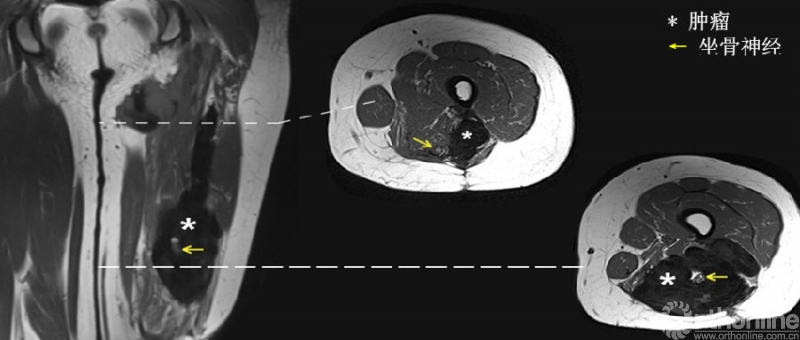

患者女,23岁,左大腿复发性硬纤维瘤,观察期间肿瘤进展。

术前磁共振提示肿瘤包绕坐骨神经与腘血管。周围肌肉组织行广泛切除,坐骨神经与腘血管R2切除后行三明治隔离手术,术后55.5月随访过程中,补片隔离区域未见复发。

术前磁共振影像